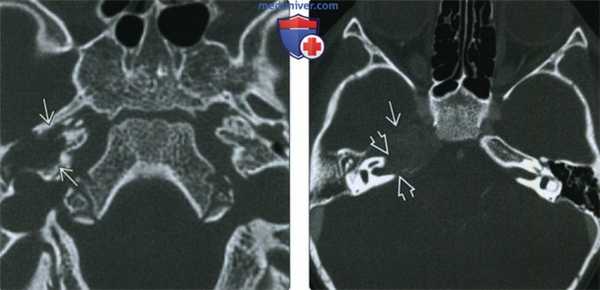

(Слева) При аксиальной КТ в костном окне у двухлетнего ребенка с хроническим средним отитом определяется литическое поражение вершины пирамиды справа. Вначале при биопсии не было выявлено признаков злокачественной опухоли или лангергансоклеточного гистиоцитоза. Эта РМС височной кости оставалась стабильной восемь месяцев.

(Справа) При аксиальной КТ в костном окне у этого же пациента (с отрицательными данными ранее выполненной биопсии), у которого сейчас на фоне роста патологического очага в вершине пирамиды развился паралич лицевого нерва справа, определяется выраженная деструкция вершины пирамиды справа с тотальной эрозией стенок правого внутреннего сонного канала.